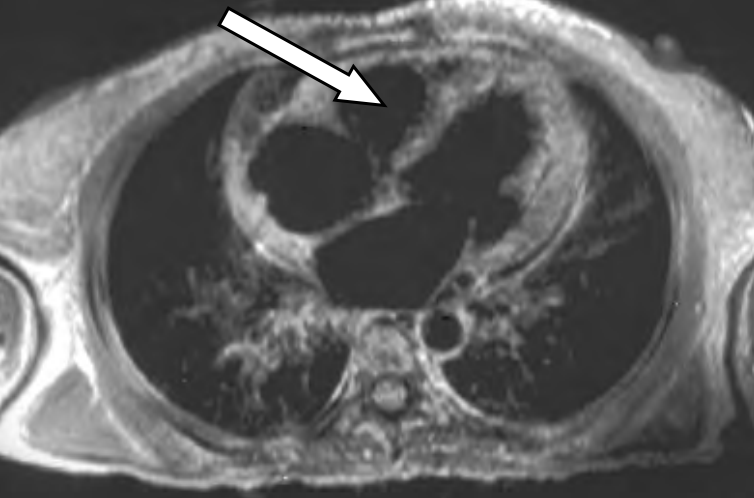

Na obrazie TK zaznaczono zatokę

Ilustracja do pytania 16

A. czołową w przekroju czołowym.

B. czołową w przekroju strzałkowym.

C. szczękową w przekroju strzałkowym.

D. szczękową w przekroju czołowym.